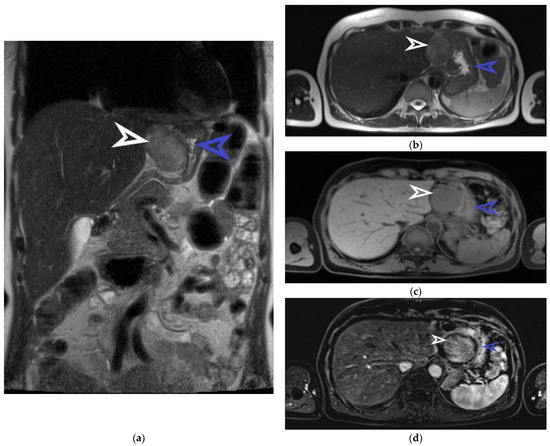

Figure 2.

Abdominal MRI examination, coronal section. The well-defined tumor originating from the anterior gastric wall with a heterogeneous T2 intermediate signal is marked with a white arrow. The stomach is indicated by the blue arrow (a). Abdominal MRI examination, transverse section, and T2 sequence. The tumor is marked with a white arrow and the stomach is marked with a blue arrow (b). Abdominal MRI examination, transverse section, and T1 sequence. The tumor is indicated by the white arrow and the stomach is indicated by the blue arrow (c). Abdominal MRI examination, transverse section, and T1 arterial sequence. The tumor is marked with a white arrow and is shown to have a hypo-signal T1, gadofil, and slightly restricted diffusion. The blue arrow indicates the stomach (d). The patient was examined and treated in the Brașov County Emergency Clinical Hospital and in the Emergency Hospital of Craiova between November and December 2022. She is not on any medication at present nor on any proton pump inhibitors. She has been in menopause for a couple of years, had 2 natural births, and had her first menstruation at the age of 15. The laboratory exams did not reveal any pathological changes, as she had a hemoglobin value of 14.8 g/dL, red blood cells 5 × 106/uL, white blood cells 6.54 × 103, INR 1.01, APTT 21.7 sec, urea 43 mg/dL, and creatinine 0.86 mg/dL. The patient later underwent an abdominal MRI for the characterization and determination of the tumor’s origin. This imaging examination described the tumor detected by ultrasound as round-oval. It was found to have an exophytic growth from the gastric wall, dimensions of 44/50 mm, an intermediate heterogeneous T2/T2 FS signal, hyposemnal T1, to be gadophilic, and to overall be slightly restricted in diffusion. Figure 2 captures some suggestive images of the tumor’s appearance on the MRI.